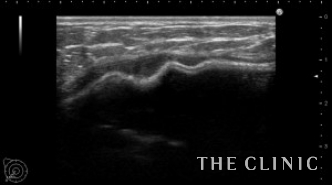

エコー所見です。

右のバッグの周囲のカプセルは肥厚して石灰化が疑われます。

わずかですが、バッグの周囲にシリコンが漏れています。